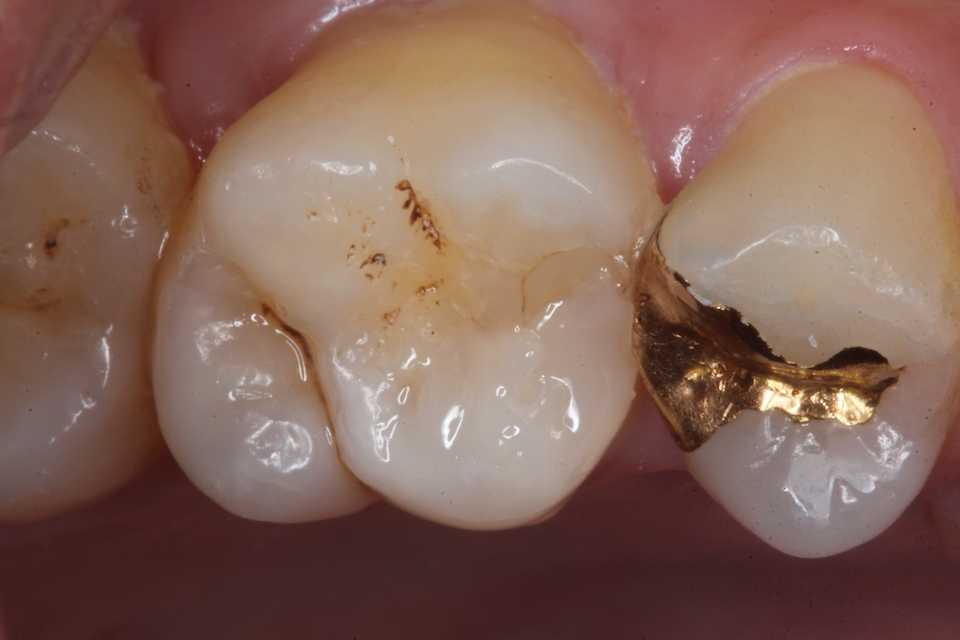

再度3MIX+α-TCPで覆罩してCR充填した。

歯肉縁下に虫歯やクラックが及んでいたができる限り取り除いた。歯肉側のエナメル質は取らざるを得なかったが、これ以上取ると大穴が開く寸前までいった。象牙質のクラックが少し見えるが、α-TCPで治って欲しい。

では時系列でどうぞ

難しかったので途中経過を撮る余裕がなかった。